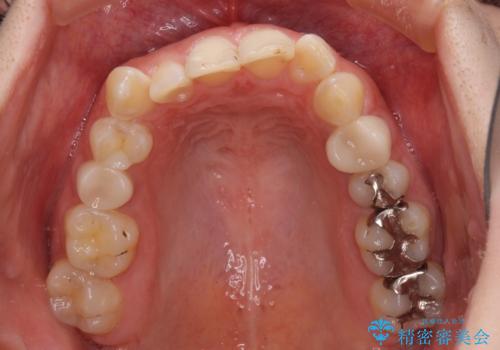

- 前歯の歯列不正を気にして来院された患者様です。

インビザラインでの矯正治療を希望されていましたが、奥歯の咬み合わせがインビザライン単独では改善困難と判断されたので、補助装置を併用することとしました。

まずは裏側の装置やワイヤー矯正を用いて歯列幅の狭い上顎を側方に拡大しつつ全体を後方に移動させ、その後インビザラインにて歯列を整えることとしました。